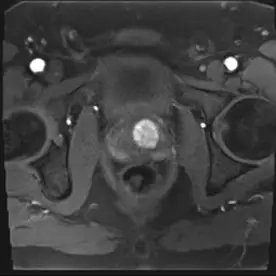

Es erfolgte eine multiparametrische MRT der Prostata mit intravenöser Kontrastmittelgabe. Neben einer Prostatahyperplasie mit ca. 47 ml Volumen zeigte sich der Nachweis von 2 malignitätssuspekten Läsionen.

Die Läsion 2 liegt in der peripheren Zone rechts apikal mit ebenfalls niedrigem Signal in T2w (Bild 3), Diffusionsstörung (Bild 4) und Korrelat in der DCE. Diese Läsion zeigt einen Kontakt zur Kapsel. Das neurovaskuläre Bündel wird hier ebenfalls nicht infiltriert. Die Läsion wurde als PI-RADS 4 klassifiziert und zeigt damit ein hohes Malignitätsrisiko.